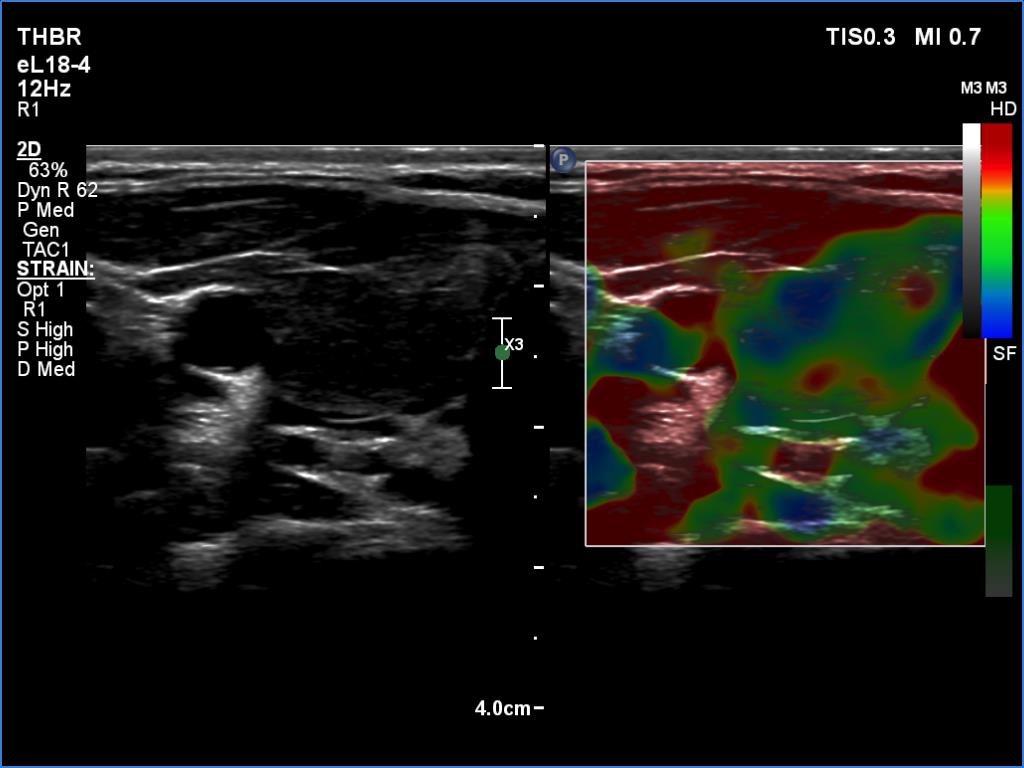

Ultrasonography. The thyroid was moderately hypoechoic and inhomogeneous. There was a deeply hypoechoic lesion in the isthmus which presented microcalcifications. Compared with the extranodular tissue, the nodule was much less vascularized on Doppler and microflow imaging but was harder on elastography.